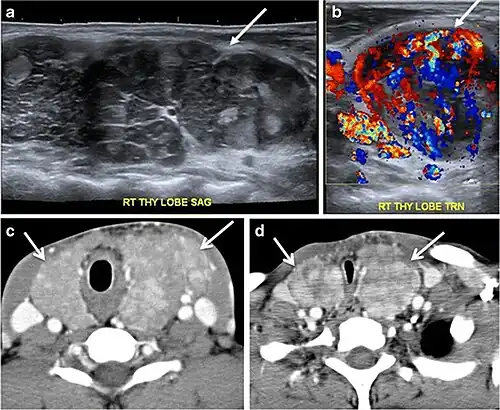

Fig. 9. A 58-year-old male patient with persistence PTC at thyroid bed with hypervascular nodal metastasis. a–c Transverse greyscale and colour Doppler neck ultrasound demonstrate hypoehoic soft tissue in the left thyroid bed (white arrow in a). There are a heterogeneous enlarged lymph nodes at level 2 and 3 with markedly increased vascularity (white arrow in b and c). d–f Enhanced axial CT images of the neck demonstrate a 2.7 × 1.4 cm hypodense soft tissue lesion anterior to the left carotid sheath (white arrow). There are left-sided enhancing abnormal and enlarged lymph nodes at cervical level 2 and 3 (black arrows).[1]